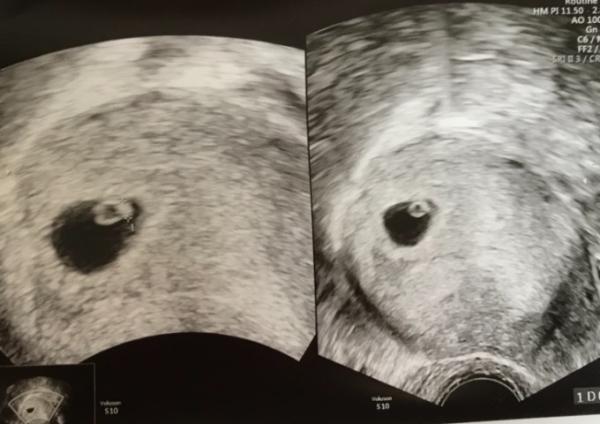

Hallo ihr Lieben, ich war heute auch bei der Ärztin. Es sieht alles gut aus. Bin ca 6+0 und das Herz hat schon schön geschlagen Termin ist der 9. Januar, wobei das beim nächsten Termin in 4 Wochen noch mal genau gemessen wird. Ich bin so erleichtert und meine Ärztin fand es auch ganz wunderbar, dass es gleich nach der Fehlgeburt wieder geklappt hat. Ich freu mich so über mein kleines Wunder

Das hört sich super an! Und das du bei 6+0 schon ein Herz gesehen hast ist echt Glück Hast du ein Bild für uns?

Ja hab ich bekommen